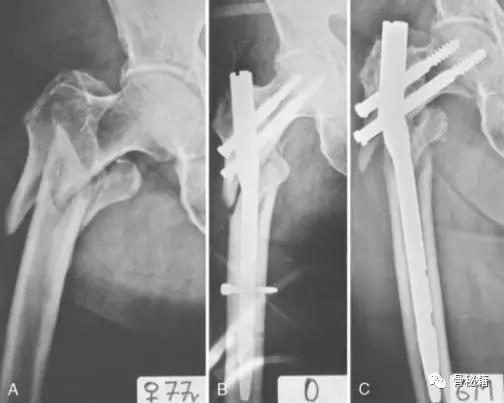

头钉过短、内侧支撑不足、导致的6周出现内翻,最后肢体短缩2cm,出现这些的原因,意味着骨折不稳定!初始固定没有达到应该稳定骨折的效果

2.断端断裂

断端断裂通常是疲劳断裂,也有部分外伤导致的断裂。疲劳断裂通常在好几个月到几年的时间不等。骨折长期不愈合所导致

骨折复位不良、断端无接触、没有动力化、粗隆下骨折应力较大。骨折延迟愈合,6个月的时候发生了断钉

7个月 骨折延迟愈合断钉